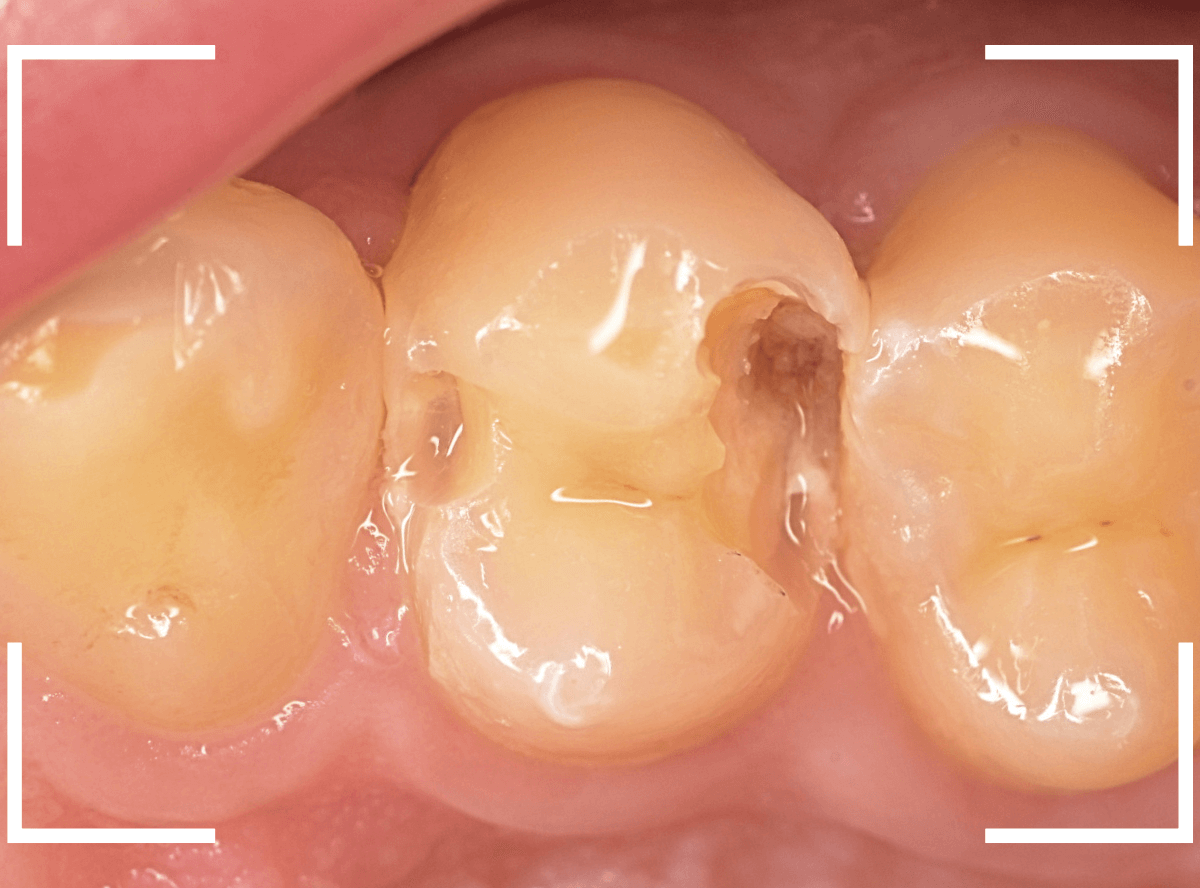

Case.24 レジンの下で虫歯が進行

上の奥歯の虫歯が見つかった患者さんです。

初診のチェックの際に、上から目視すると、レジンがつめてある〇部分が薄暗く黒くなっているので、これは虫歯があるな、とわかりました。

先ほどの黒く見えた部分は少し削るとすぐに虫歯が出てきました。

手前の歯まで虫歯を除去した時点で、う蝕検知液で確認します。

赤く染色されている部分が虫歯です。

思ったよりも深めの虫歯ですね。

レジンを除去して虫歯をすべて治療したところです。

レジンの中も全体にうっすらと虫歯になっていました。

このくらいの虫歯でも、患者さんは自覚症状はありませんでした。